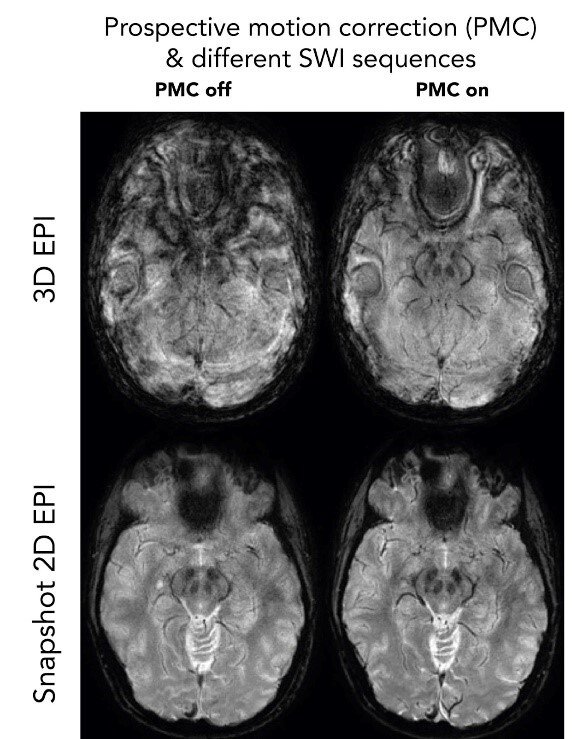

Rörelserobusta pulsesekvenser - Snapshot SWI-EPI

Trots rörelsekorrektion i realtid med Tracoline eller WRAD är det fundamentalt svårt att få bra bildkvalitet med 3D-sekvenser med lång TE som för SWI. Även med en ideal rörelsekorrektion leder de fasförändringar i hjärnan (som uppstår vill långa ekotider) till bildstörningar (överst-höger, 3D EPI). Med vår snapshot 2D SWI EPI erhålls ett komplett bildplan på 0.1 s under samma fasbetingelser i hjärnan. Med flera repetitioner av samma bildplan som medelvärdesbildas efter rörelsekorrektion ökas SNR till lämplig nivå.